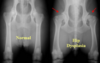

Describe hip dysplasia.

Primary changes are - Laxity of hip joints - Lack of formation of the acetabulum - Poor coverage of the femoral head Secondary changes, - Subchondral sclerosis at the cranial acetabular margin, moves laterally over time. - Osteophytes at the caudal aspect of the femoral neck (Morgan’s line). - Periarticular osteophyte formation on the cranial effective acetabular rim and dorsal acetabular margin.

identify

hip dysplasia